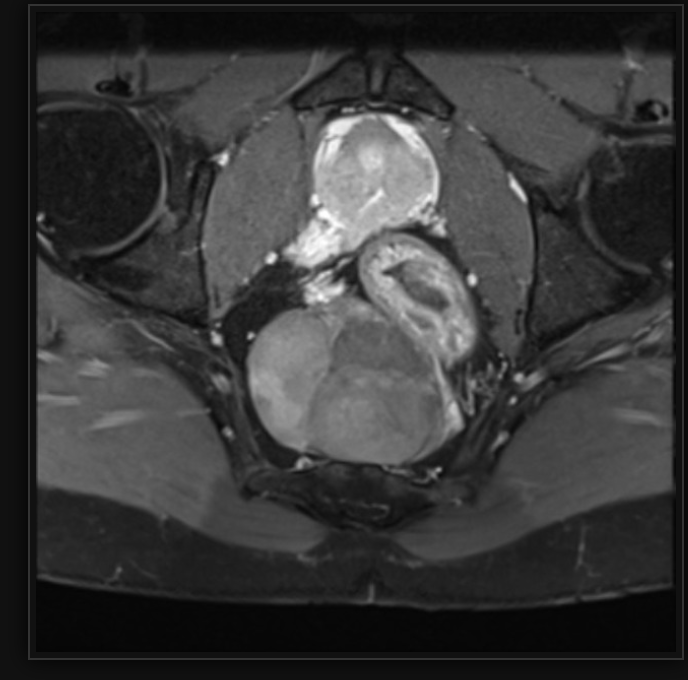

Pelvic ultrasound

streaky uterus

streak ovary